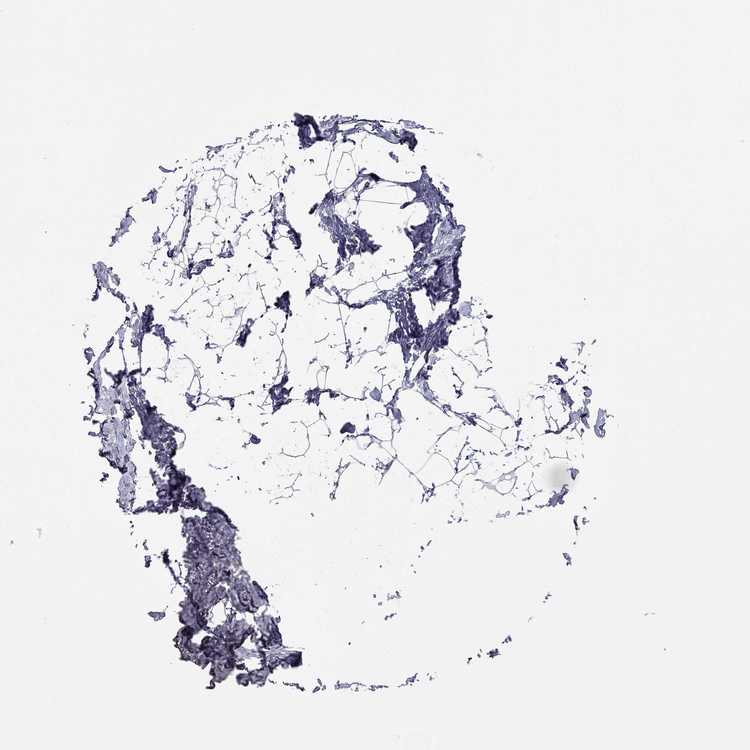

TISSUE PRIMARY DATA BREAST Show tissue menu

BREAST - Antibody stainingi

Antibody staining in the annotated cell types in the current human tissue is reported as not detected, low, medium, or high, based on conventional immunohistochemistry profiling in selected tissues. This score is based on the combination of the staining intensity and fraction of stained cells.

Each image is clickable and will lead to virtual microscopy that enables deeper exploration of all samples and also displays staining intensity scores, fraction scores and subcellular localization as well as patient and tissue information for each sample.

Antibody HPA013613Antibody HPA016934

Myoepithelial cells Not detectedHigh